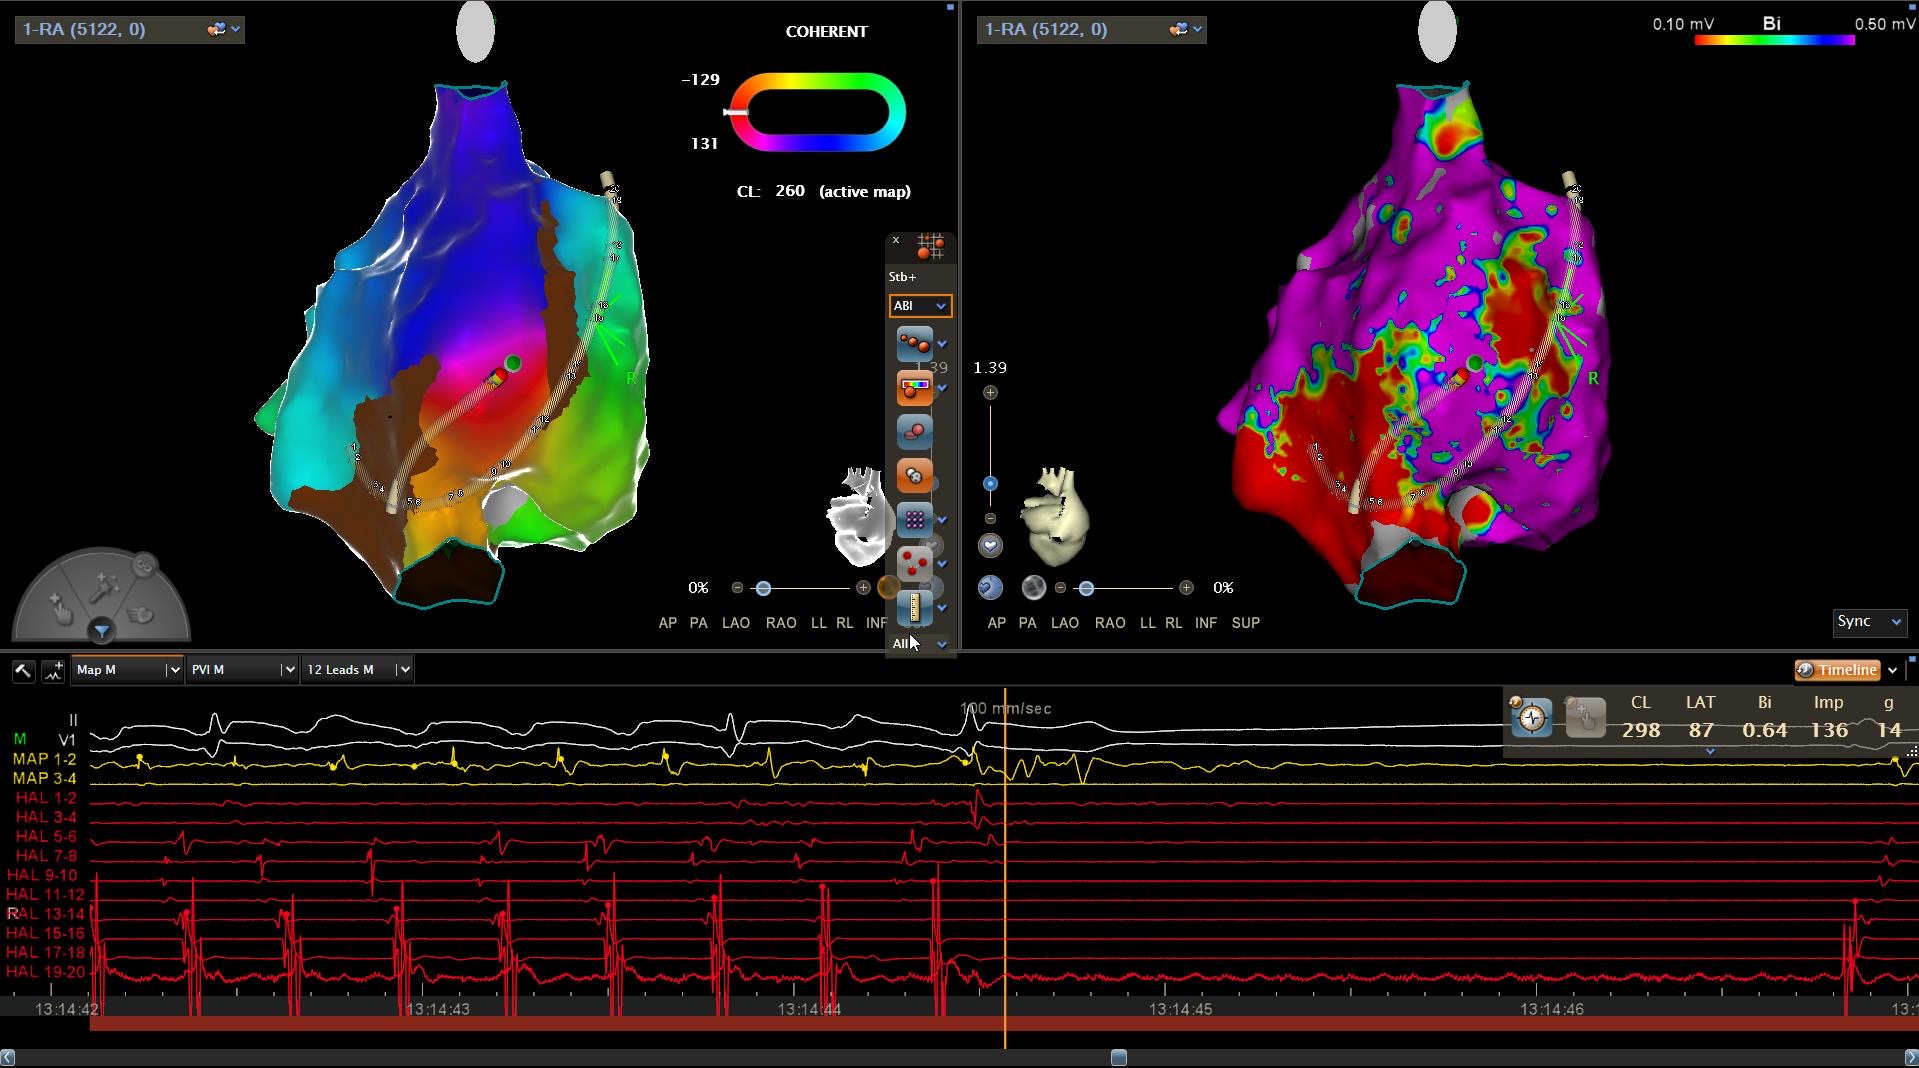

Objetivos: Caracterizar los aleteos auriculares atípicos (AAA), así como desc...